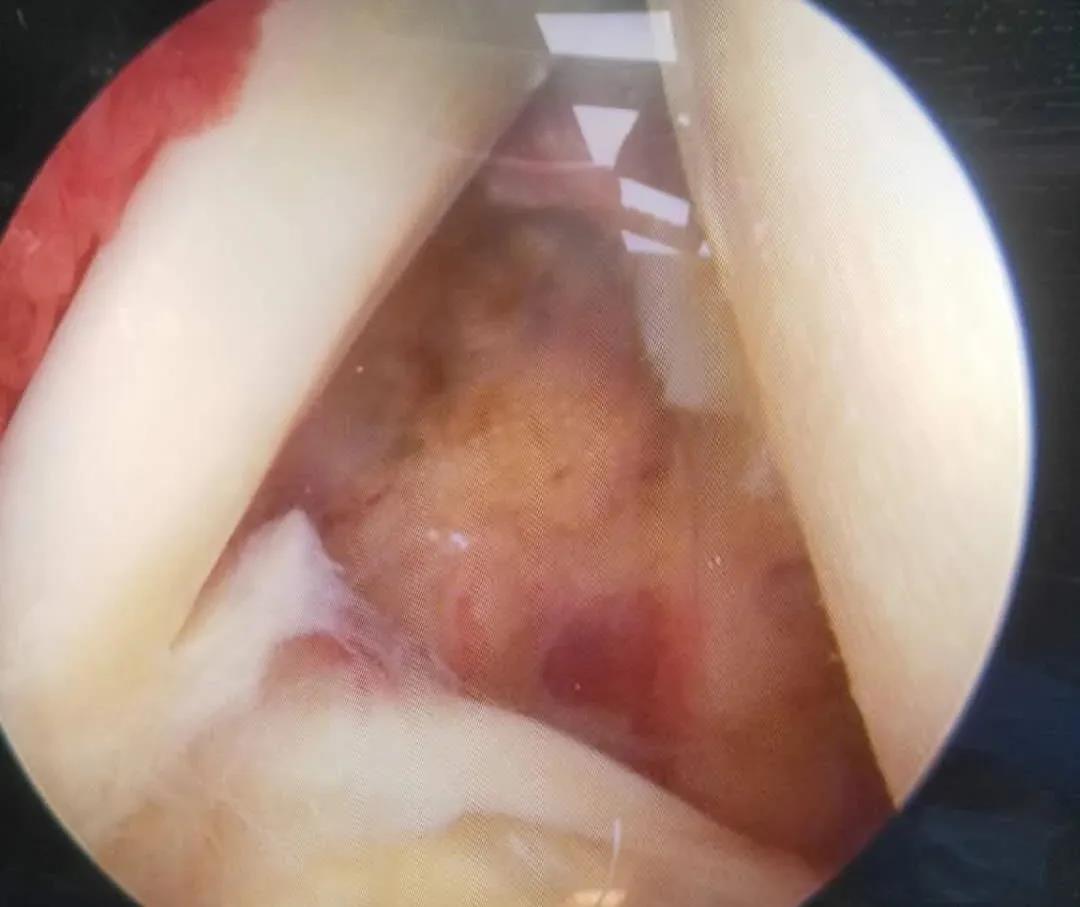

膝骨關(guān)節(jié)炎患者是臨床常見的老年關(guān)節(jié)疾病,骨二科根據(jù)患者病情綜合評估考量,對較年輕患者采用膝關(guān)節(jié)鏡清理加腓骨截骨術(shù),對脛骨近端內(nèi)翻畸形且外側(cè)關(guān)節(jié)間隙良好的患者采用膝關(guān)節(jié)鏡清理加脛骨近端高位截骨術(shù)或單髁置換術(shù),恢復(fù)患者膝關(guān)節(jié)正常力線,減緩或避免最終的膝關(guān)節(jié)置換治療。

腓骨截骨術(shù)